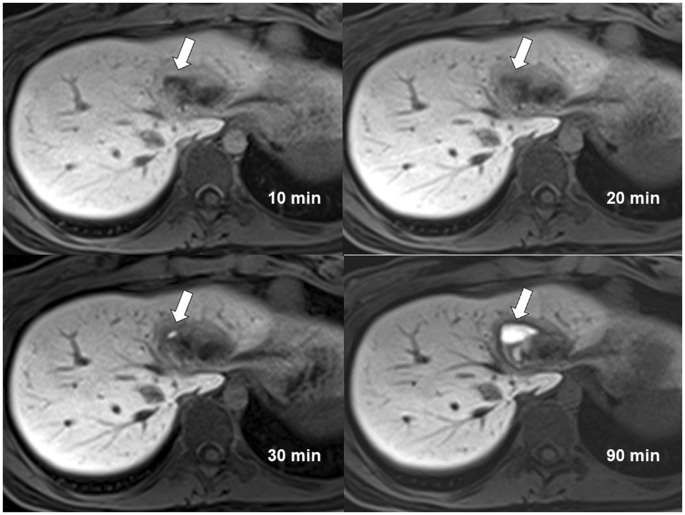

Bile leak on CEMRC

The scores on bile leak detection among three readers increased from CEMRC acquired at 10 minutes to CEMRC acquired at 90 minutes (Fig. 2). The AUROC of the three readers for bile leak detection on CEMRC of different acquisition time points tabulated in Table 2 also increased significantly from 10 minutes to 90 minutes. The AUROC acquired at 90 minutes by three readers were 0.824, 0.914 and 0.929 respectively and the inter-rater reliability was very good with an ICC of 0.816. Although the ICC was higher (0.821 versus 0.816) for CEMRC acquired at 30 minutes than that acquired at 90 minutes, the AUROC for bile leak detection by the three readers on CEMRC acquired at 30 minutes were not only small but also statistically nonsignificant.

Contrast enhanced MR cholangiography of a 20-year-old woman with a liver injury acquired at 10 minutes, 20 minutes, 30 minutes and 90 minutes. Type I bile leak confined within liver parenchyma is most obviously detected at 90 minutes acquisition (arrow). The average scores given by three readers are 1.33 (10 minutes), 2.00 (20 minutes), 2.00 (30 minutes), 5.00 (90 minutes).